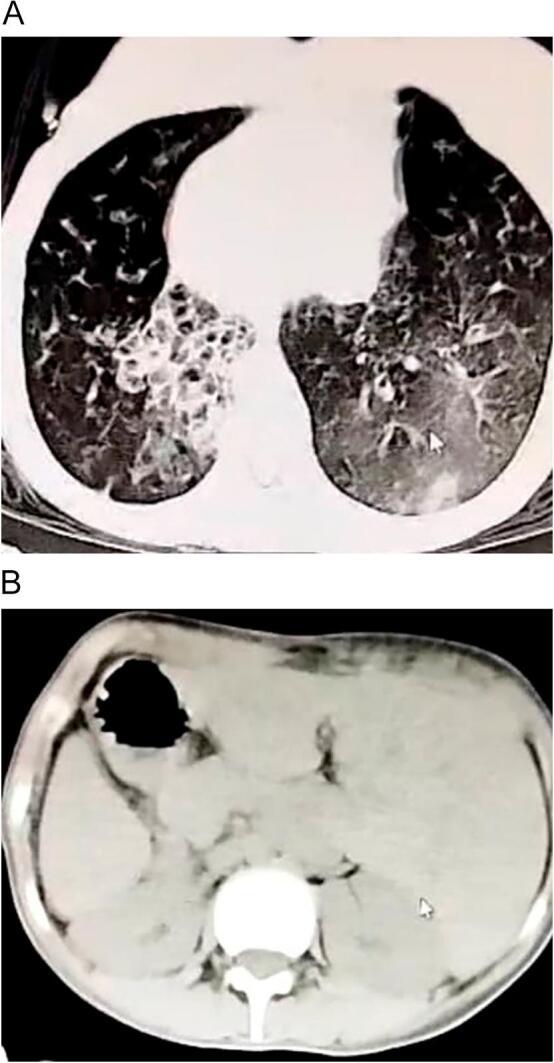

We present the case of a female patient with a history of recurrent respiratory infections since birth, treated with antibiotics and complicated by middle ear disease. Investigations revealed a rare presentation of air bullae associated with bronchiectasis. The patient was referred to our care and diagnosed with Kartagener syndrome, subsequently undergoing urgent surgical intervention, which contributed significantly to her overall improvement and the resolution of her thoracic condition.

我们报告一例女性患者,自出生以来有反复呼吸道感染病史,接受过抗生素治疗,并伴有中耳疾病。检查发现一种与支气管扩张相关的罕见肺大疱表现。该患者被转诊至我们处并被诊断为卡塔格内综合征,随后接受了紧急手术干预,这对她的整体康复以及胸部疾病的缓解有显著帮助。